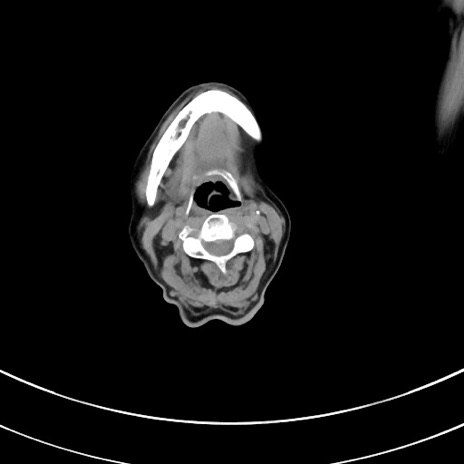

冠状断像